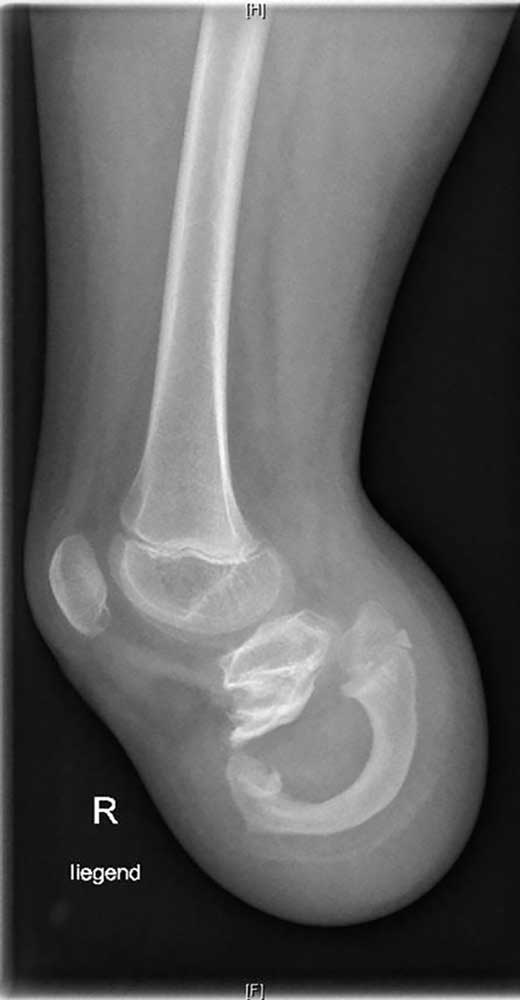

Es handelt sich um ein 9‑jähriges Mädchen, dem im Rahmen einer Streptokokkensepsis im Alter von 4 Jahren beidseitig die Unterschenkel amputiert wurden. Durch die frühe Amputation entstand eine sehr kurze Tibia, die sich im weiteren Verlauf jedoch nicht weiterentwickelte. Erfreulicherweise hat sich aber die Fibula durch die besondere Belastung und den „Prothesendruck“ der Tibia quasi unterstellt (Abb. 2). Somit ist nicht nur eine ausreichende Stumpflänge zur Prothesenversorgung, sondern auch eine ausreichende Stabilität gegeben, wodurch das Kniegelenk funktionell erhalten bleibt. Zwar müssen dabei aufgrund der sehr kurzen und eigentümlichen Hebelverhältnisse bestimmte Einschränkungen hinsichtlich der Kraftübertragung zwischen Stumpf und Schaft in Kauf genommen werden, und die Bettung des Stumpfes erfordert besondere Modelltechniken, die nicht analog zu einem klassischen Stumpf sind, aber es ergeben sich doch gute funktionelle Ergebnisse. Dennoch bedarf es einer engen Anbindung an das Versorgungsteam und einer engmaschigen Kontrolle der Patientin im weiteren Verlauf, um potenziell negativen Entwicklungen rechtzeitig begegnen zu können.